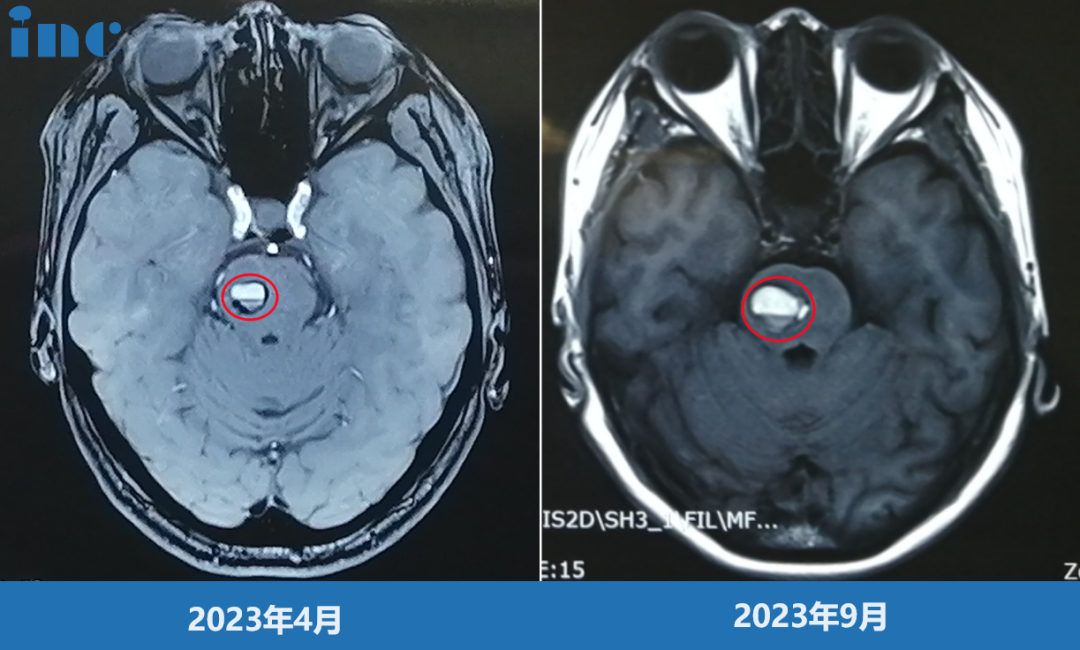

经过两年随访期,影像学检查显示海绵状血管瘤体积从初始0.8厘米增大至2.0厘米,且出现反复出血现象。出血频率逐渐增加,间隔期缩短,伴随出现头晕、眼肌痉挛、耳部不适等神经系统症状。脑干海绵状血管瘤的主要风险在于反复出血导致的神经功能损害,出血后形成的含铁血黄素沉积可对周围神经组织产生持续性化学刺激。